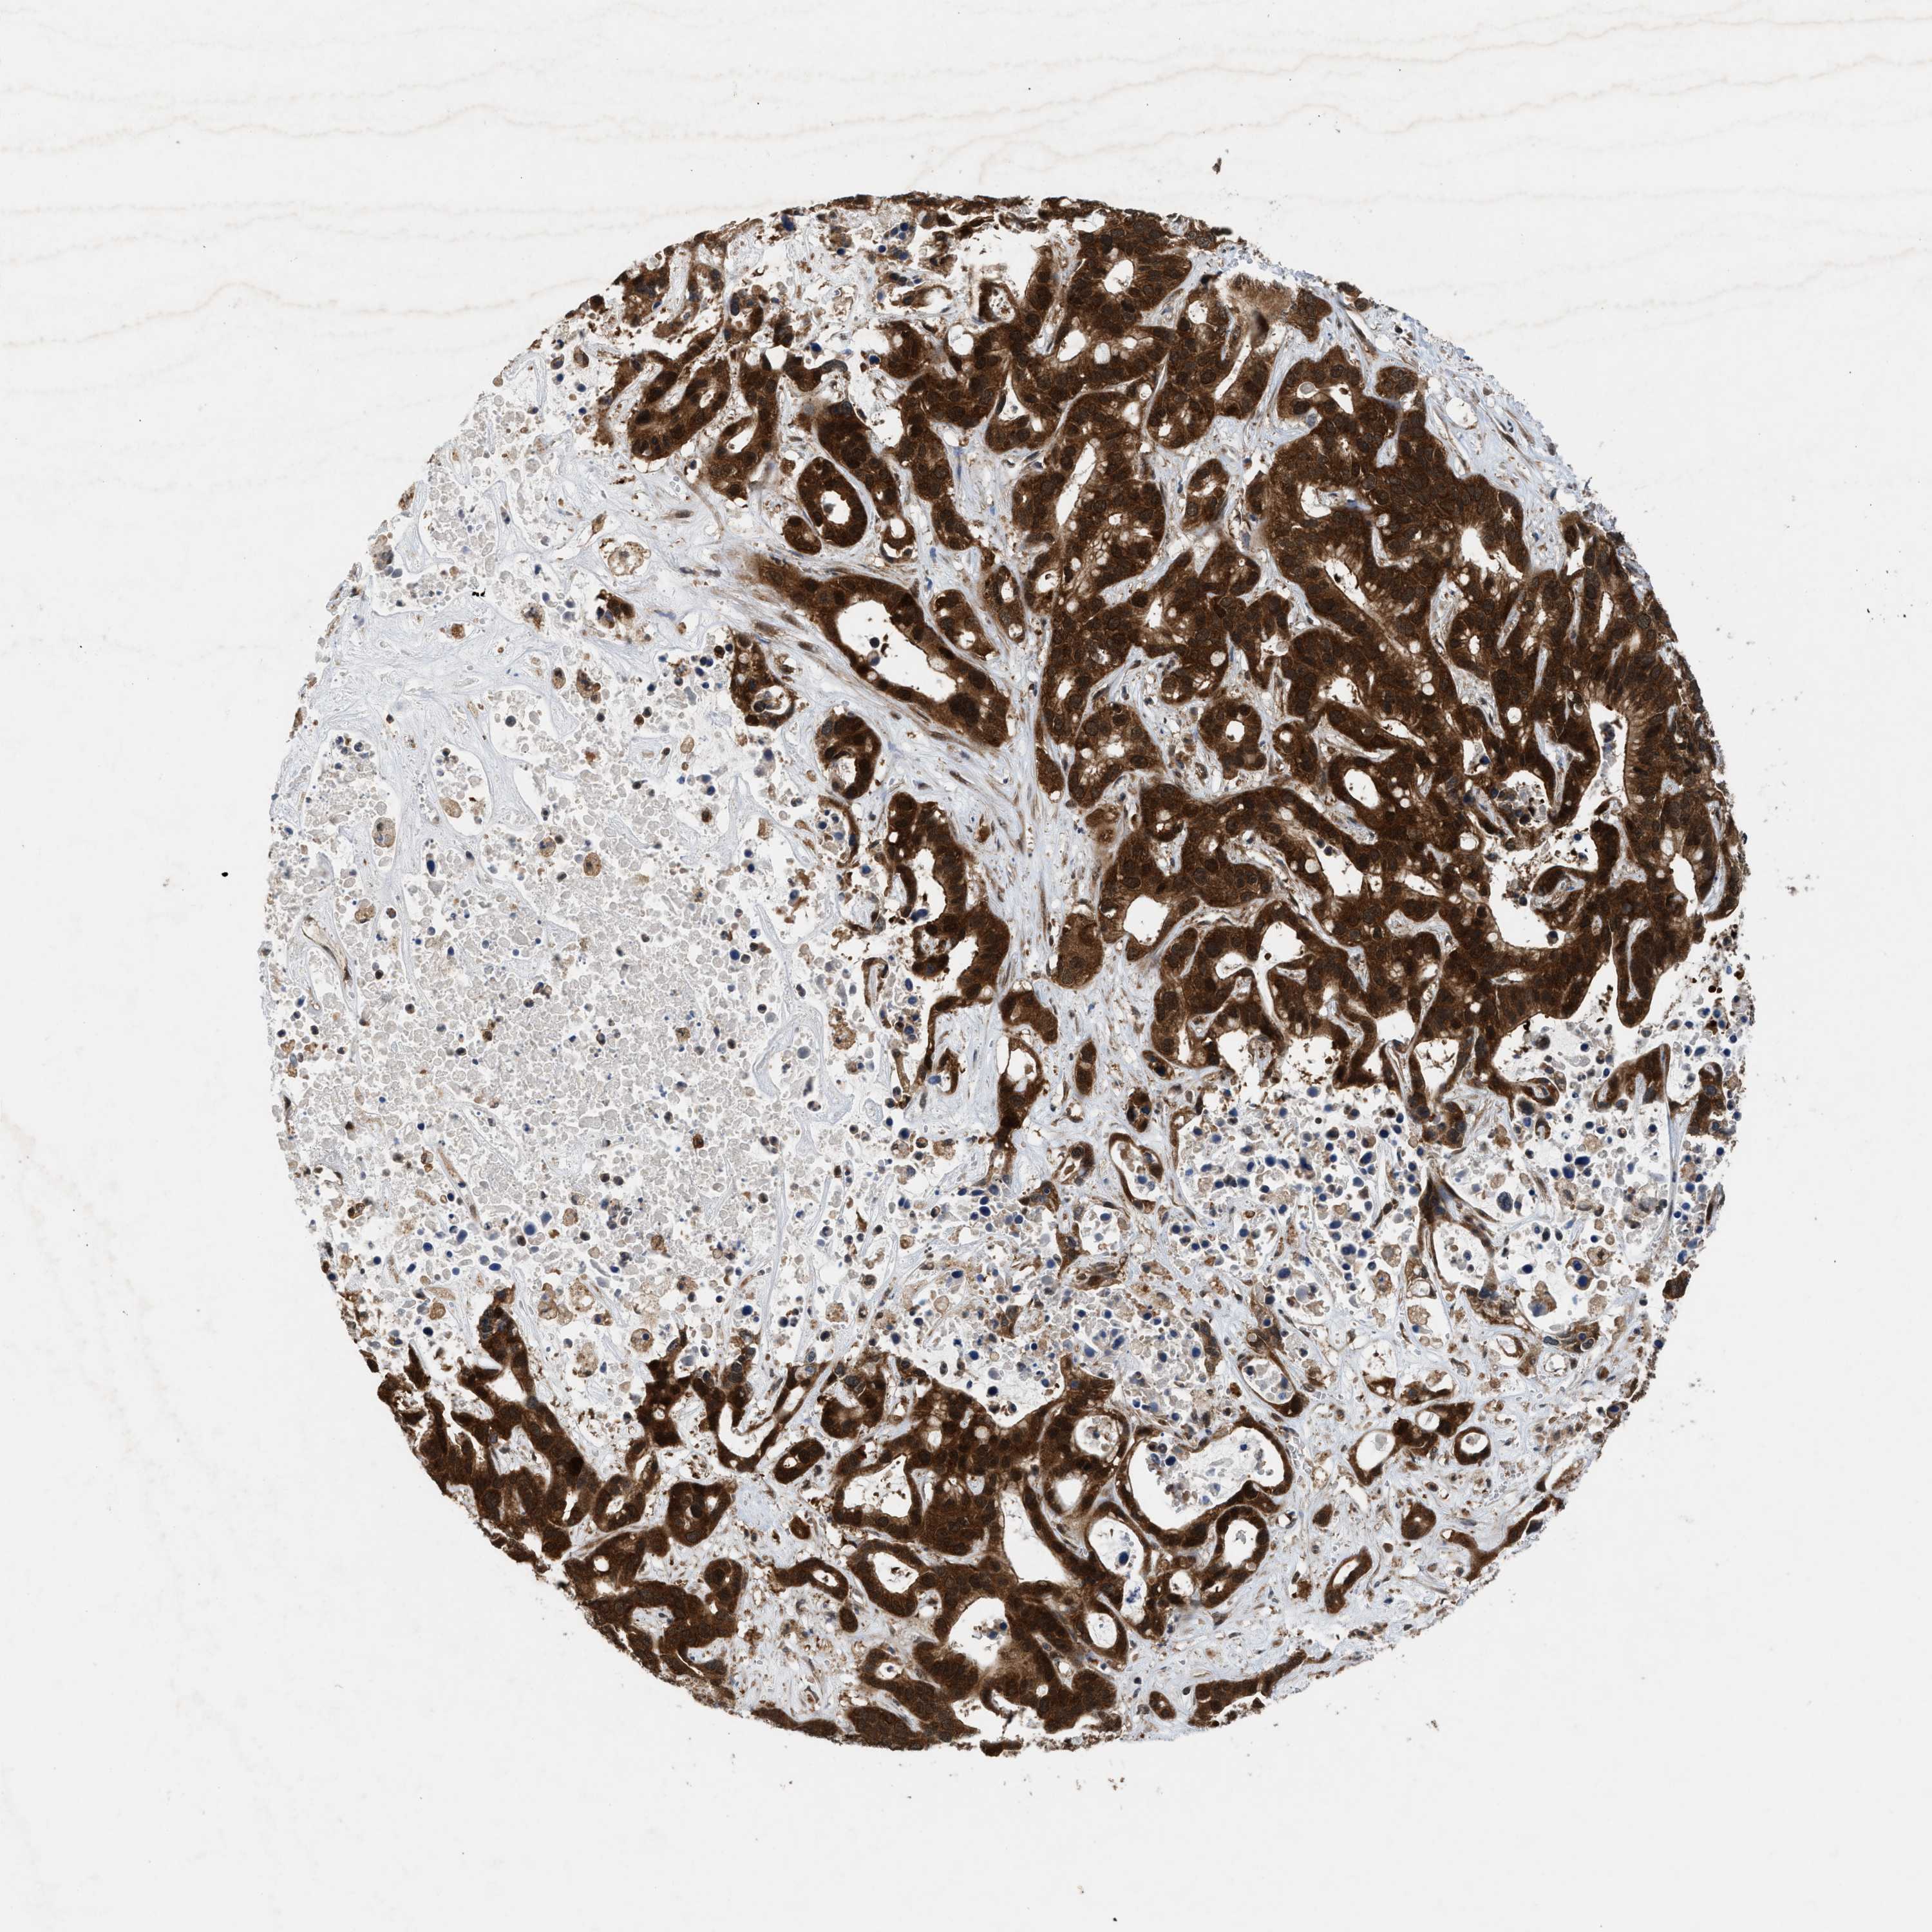

LIVER CANCER - Protein expressioni

A mouse-over function shows sample information and annotation data. Click on an image to view it in a full screen mode. Samples can be filtered based on level of antibody staining by selecting one or several of the following categories: high, medium, low and not detected. The assay and annotation is described here.

Note that samples used for immunohistochemistry by the Human Protein Atlas do not correspond to samples in the TCGA dataset.

Antibody stainingi

Antibody staining in the annotated cell types in the current human tissue is reported as not detected, low, medium, or high, based on conventional immunohistochemistry profiling in selected tissues. This score is based on the combination of the staining intensity and fraction of stained cells.

Each image is clickable and will lead to virtual microscopy that enables deeper exploration of all samples and also displays staining intensity scores, fraction scores and subcellular localization as well as patient and tissue information for each sample.

Antibody HPA008237

Antibody CAB017181

Staining

High

Medium

Low

Not detected

Intensity

Strong

Moderate

Weak

Negative

Quantity

>75%

75%-25%

<25%

None

Location

Nuclear

Cytoplasmic/membranous

Cytoplasmic/membranous,nuclear

Cholangiocarcinoma

Carcinoma, Hepatocellular, NOS